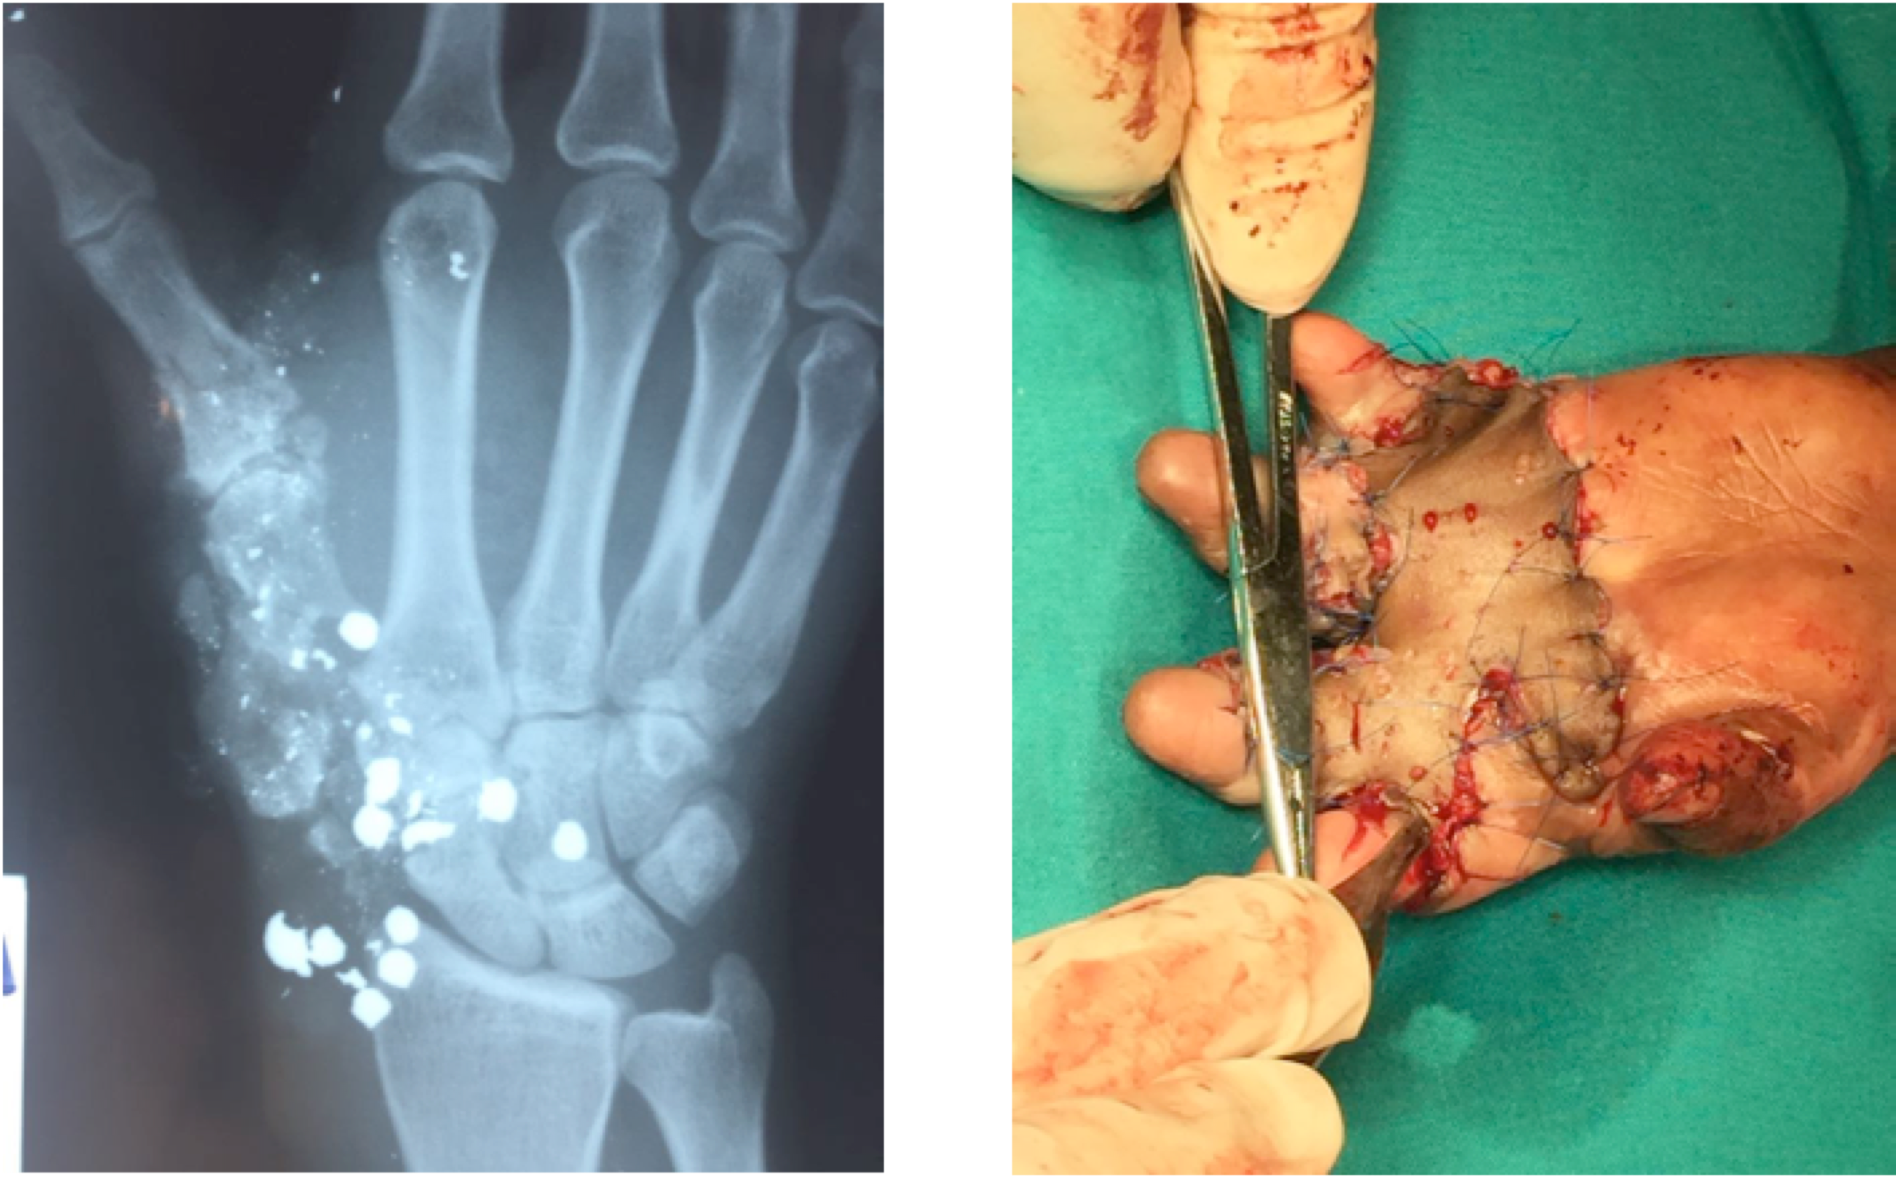

La presión asistencial ha sido menor, pero hemos tenido casos de especial complejidad y gracias a la presencia del Dr. Tabuenca - superespecialista en cirugía de la mano - hemos podido resolver un caso de mano catastrtófica por herida por arma de fuego y la secuela de una quemadura en la mano en una niña de dos años y medio que tenía la mano izquierda completamente cerrada